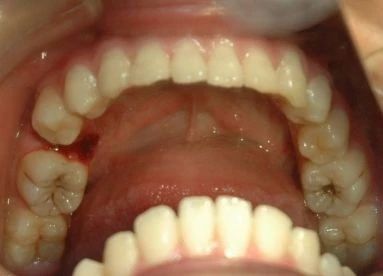

拔牙后出血要立即就医查清出血的原因,然后再针对不同情况给予处理。如果只是创口局部出血,那么医生会进行局部处理;如果是全身性因素导致的出血(如血液病、肝病等),除了要进行局部处理,还要根据不同症状表现进行全身治疗。